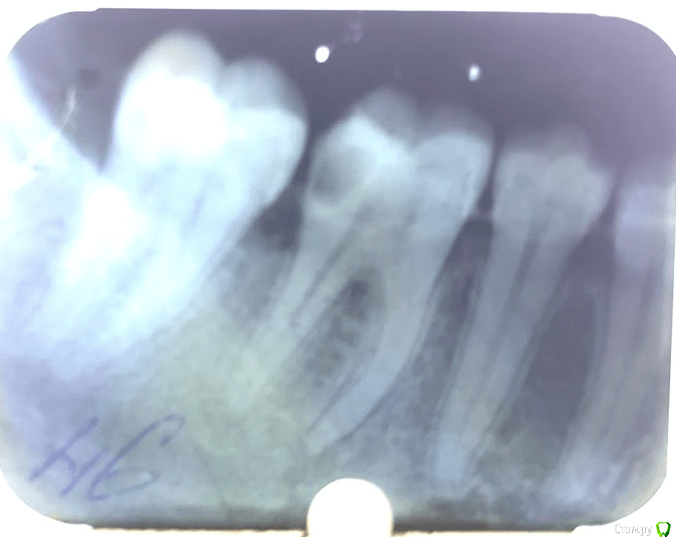

Евгений Семченок Опубликовано 26 мая, 2019 Поделиться Опубликовано 26 мая, 2019 26.02.16 вылечила 46 зуб, нерв не удаляли,обработали полость, поставили постоянную пломбу. 26.05.19 зуб начал болеть, обратилась повторно к другому врачу. Вскрыли пломбу и сказали, что воспалительный процесс начался из за неправильного лечения при первом обращении с этим зубом. Якобы при жалобах такого характера и таком снимке удаление нервов нужно проводить сразу и в этом случае зуб бы не воспалился и не потребовалось бы повторного лечения. Прошу специалистов помочь разобраться. Фото со снимками при первом и повторном обращении приложила, так же во вложении фото из карточки с жалобами и диагнозом при первом посещении. Ссылка на комментарий